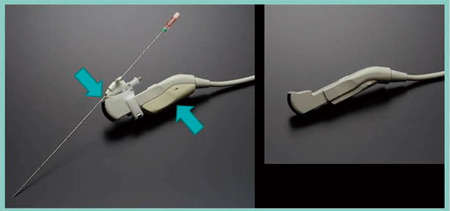

■穿刺用マイクロコンベックスプローブ「EUP-B712」

新しい穿刺用マイクロコンベックスプローブ「EUP-B712」を紹介する(図3)。形状は,穿刺しやすいように工夫されている。1つはアタッチメントを装着する面に切れ込みをつけることで,音響レンズ面のすぐ横から針を出すことができ,死角なく針を認識することができる。もう1つは,磁場センサ内蔵の持ち手を装着すると,握る手と針が触れる心配がなく,しっかりとプローブを固定することができる。

図3 穿刺用マイクロコンベックスプローブ EUP-B712

画質も優れており,Bモードでは約15cmの深さまで観察が可能である。10cmを超えると画像が流れはするものの,細い血管まで描出可能で,深部に非常に強い。造影超音波Kupffer相で肝癌の穿刺をすることが多いが,深部にフォーカスすることで高いコントラストが得られ,MI値を調節することで肝表面も明瞭に観察できる。Kupffer相における高音圧フラッシュの欠損像は,深部までしっかりと観察することができ(図4),Kupffer相でのストレスのない穿刺が行えると期待される。